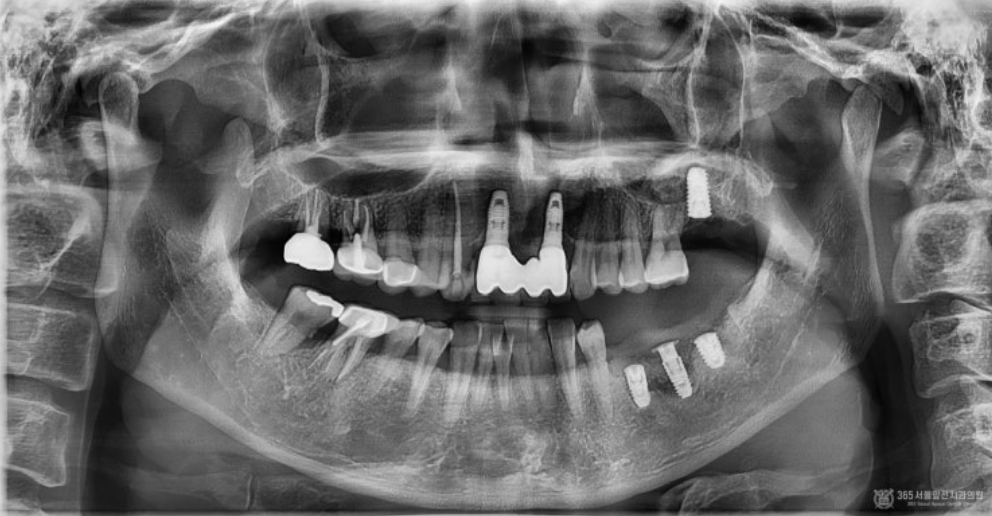

촬영일시 : 2024.05.19 X-ray 사진(위 이미지)상 오른쪽 아래(실제 입안에서는 왼쪽 아래 부위) 어금니 부위에 염증이 심하게 온 임플란트와 해당 임플란트 옆에 심한 치주염으로 발치가 된 자리가 보입니다. 또한 수술 전 CT 사진(아래 이미지) 을 찍어보니 마치 폭탄을 맞은듯하게 뼈가 웅덩이처럼 파여있는 모습이 관찰됩니다. 게다가 제거해야할 임플란트 아래쪽으로 신경이 지나가는 구멍이 있어서 수술을 할때 매우 주의해야하는 상황이었습니다. 두 자료를 를 종합해서 볼 때 뼈가 아래쪽으로 움푹 파여있어서 주변부위와 뼈의 높이를 맞춰주면서 염증에 이환된 임플란트를 제거하고 새로 식립하는 수술을 계획하였습니다.